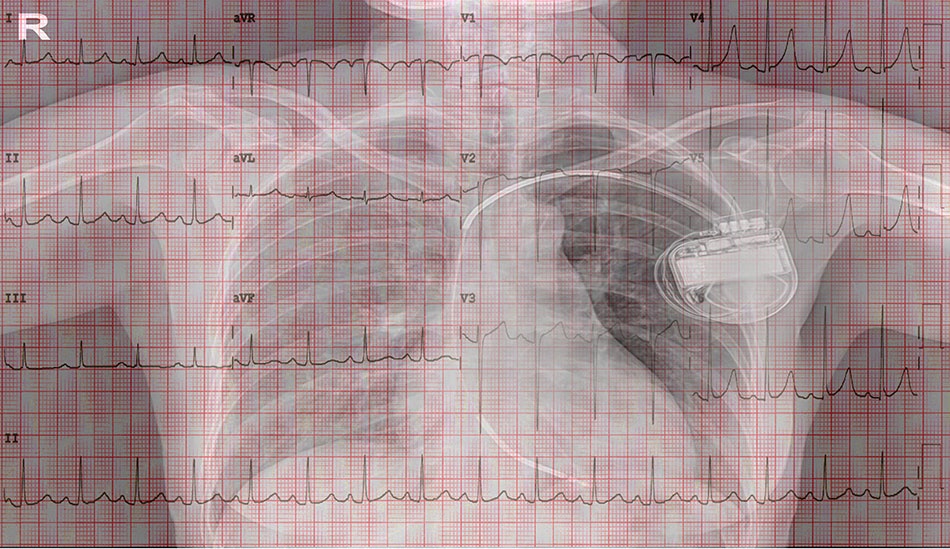

Theo đại diện Chuyên khoa Tim của Bệnh viện FV, thủ thuật đặt máy tái đồng bộ nhịp tim 3 buồng (CRT) là thách thức trong điều trị loạn nhịp và suy tim, đòi hỏi kỹ thuật cao cùng trang thiết bị hiện đại.

Cấy ghép máy tái đồng bộ nhịp tim - giải pháp mang lại cơ hội sống cho bệnh nhân.

Bác sĩ Minh cho biết trên thế giới, tỷ lệ thành công của thủ thuật này khoảng 70%, tức cứ 10 người được gắn máy thì có 7 người thành công và 3 người không đáp ứng (do máy không hoạt động hoặc không đồng bộ với quả tim).

Theo bác sĩ Minh, việc đặt máy tái đồng bộ nhịp tim là kỹ thuật khó, đã cứu sống nhiều bệnh nhân suy tim. Tuy nhiên, kỹ thuật này chỉ có thể thực hiện với sự hỗ trợ của thiết bị hiện đại.